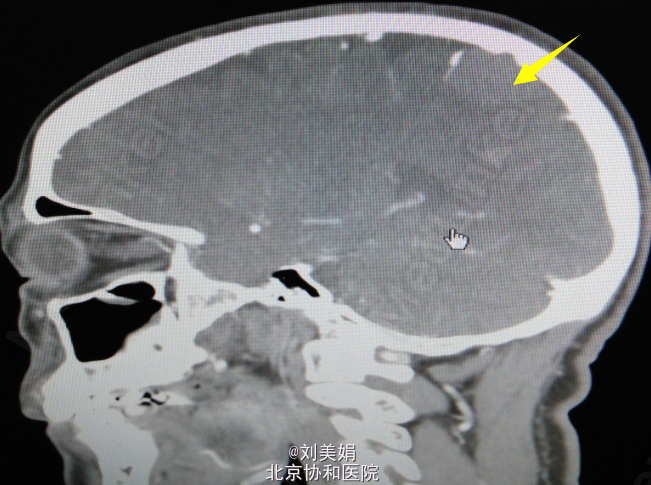

头增强CT:平扫图象显示:左侧顶部见一圆形略高密度影,边缘光整,边界清晰,大小约28.2mm×23.7mm,CT 值 68.2Hu,其内未见钙化,周围脑回受压、塌陷,脑室系统无扩大,脑沟裂未见增宽。中线结构未见明显移位。 增强图象显示:病灶明显均匀强化。CT 值为 92Hu,密度均匀,边缘清晰。右侧筛窦密度增高。